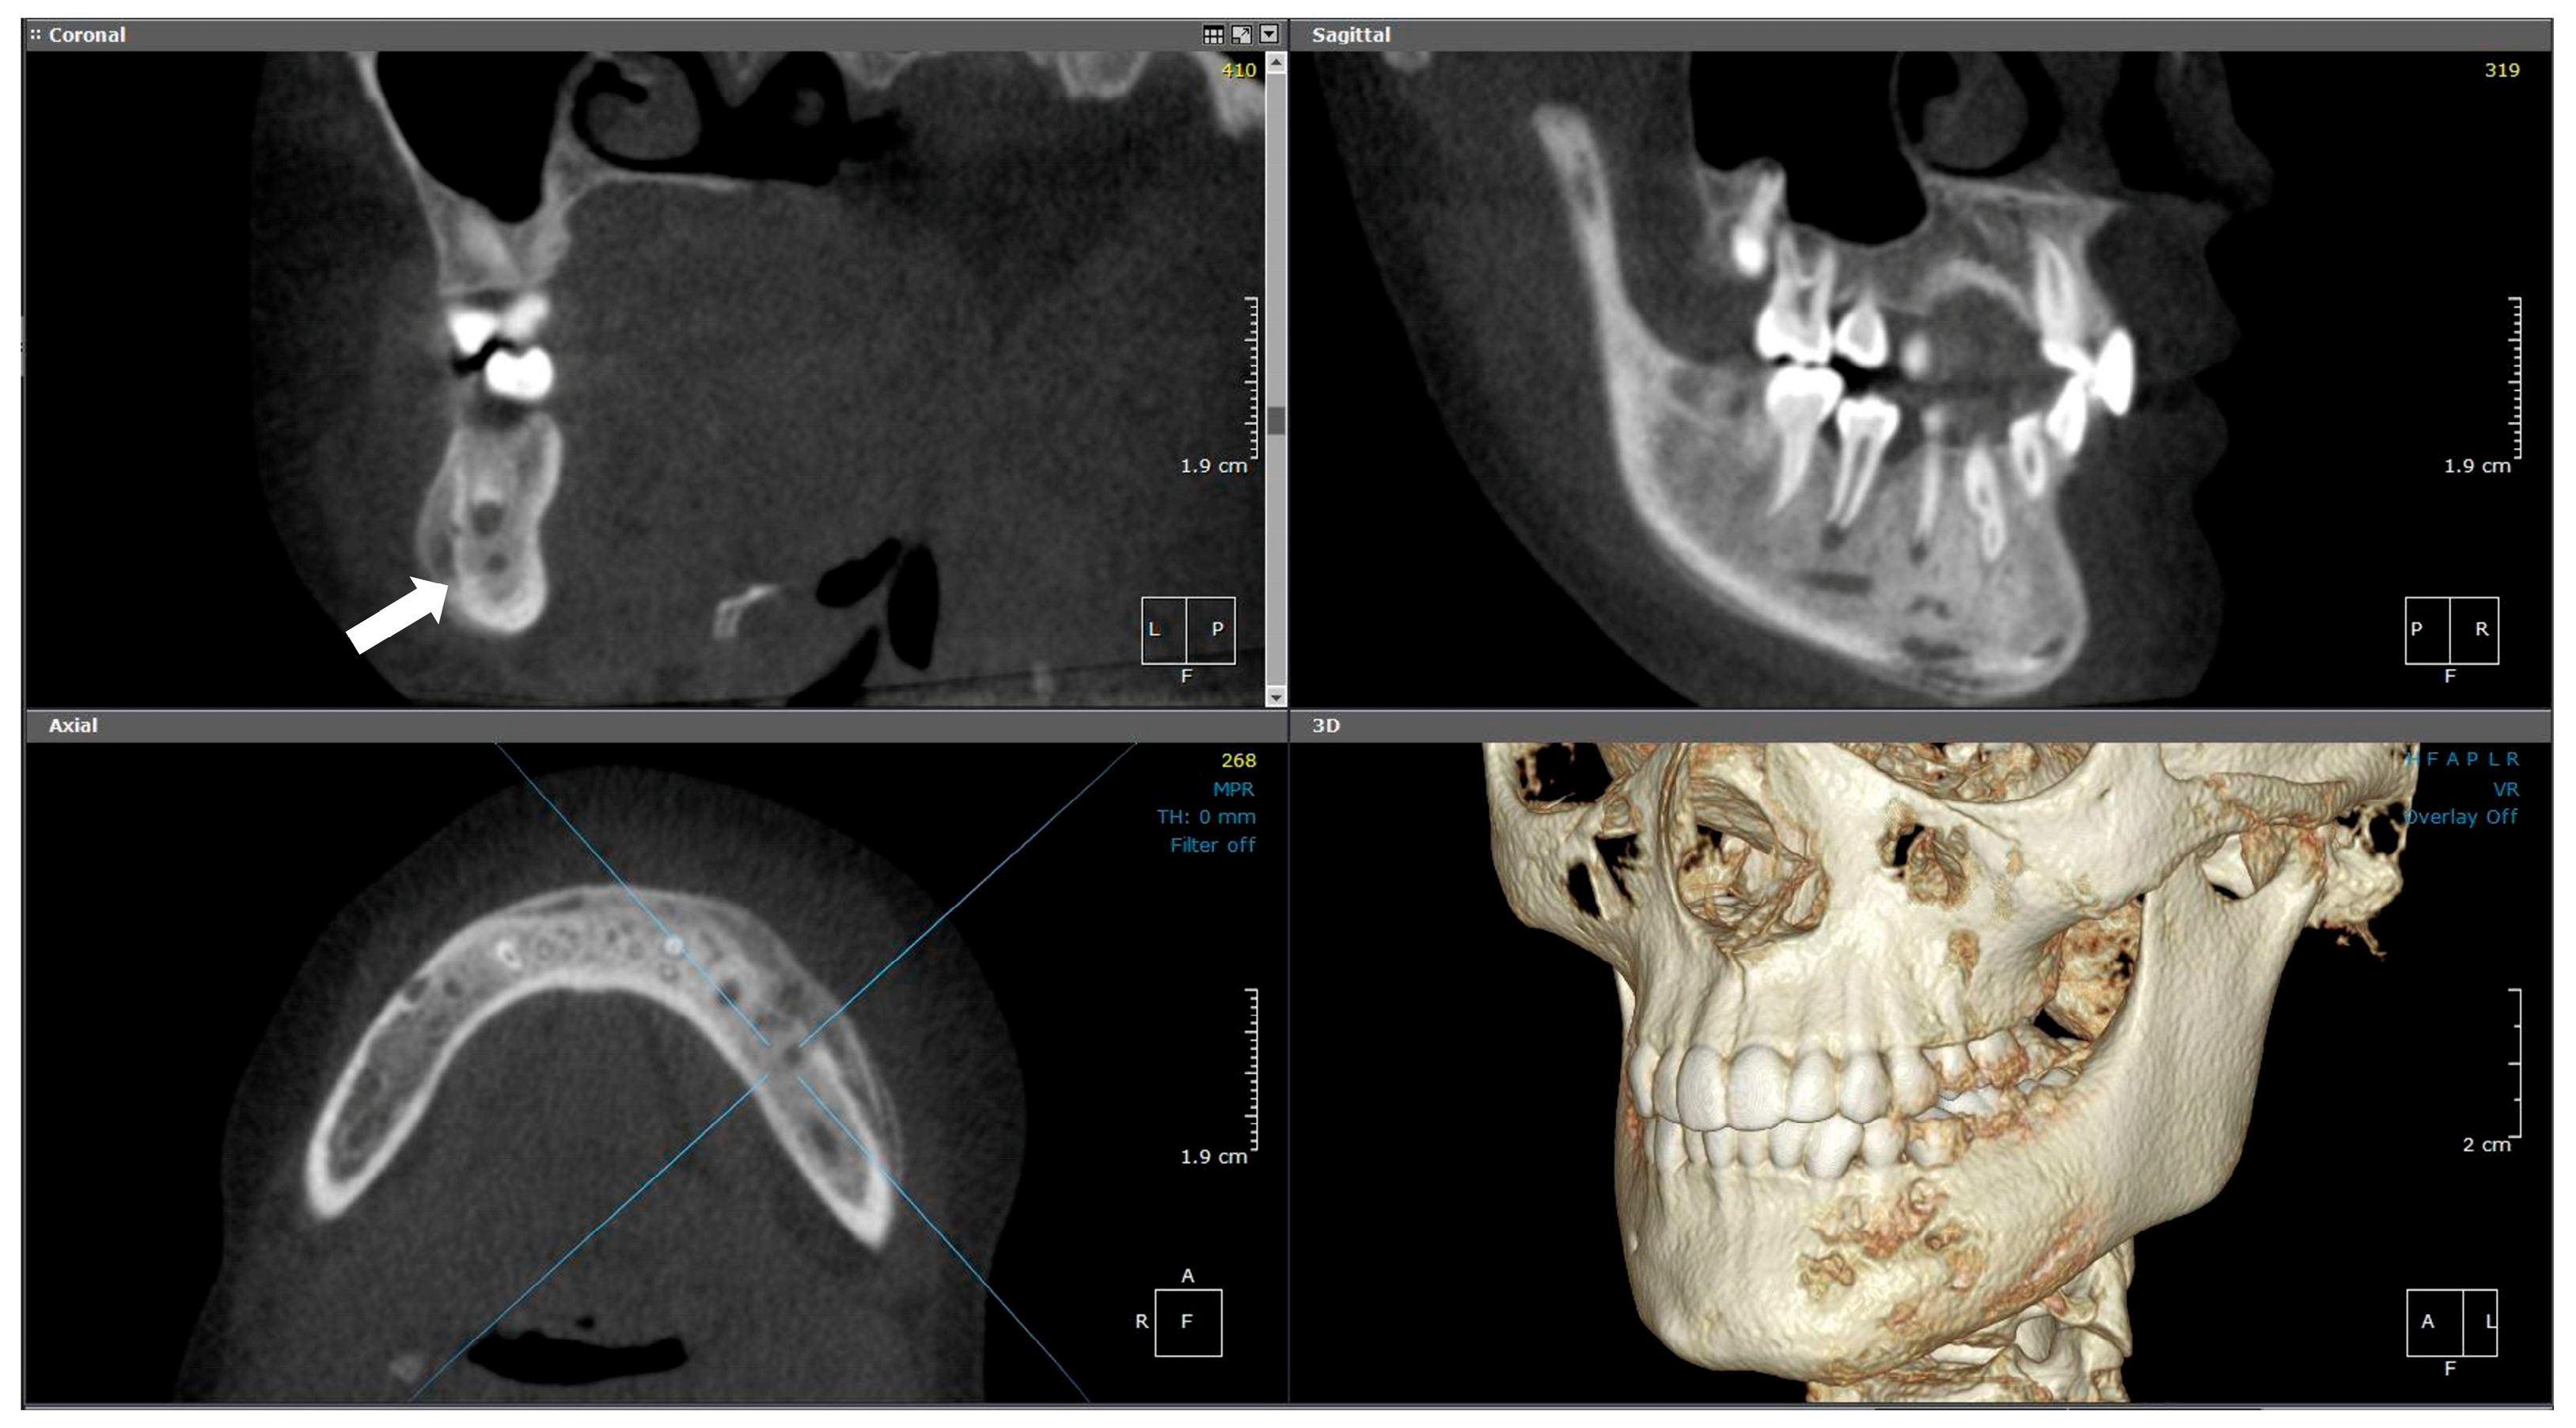

2.3.2. Radiographic Examination

| 3 | 10 | Right mandible (#34–#47, crossing midline) | Granular sclerotic and radiolucent lesion, moth-eaten pattern, layered periosteal reaction | Normal viable bone, sterile | Empirical antibiotics, paracetamol, NSAIDs | CNO confirmed by imaging, CT, and sterile biopsy | NSAIDs only; no need for further escalation | Progressive improvement; under observation |